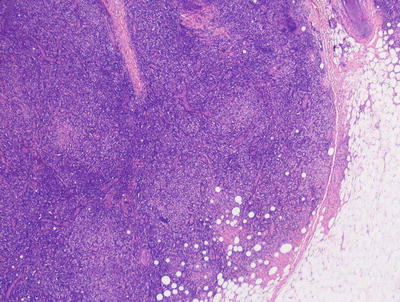

22.7.2 Histology

The cutaneous lesions in Rosai-Dorfman disease are histologically quite similar to changes described in the more common lymph node-based sinus histiocytosis with massive lymphadenopathy. A dense infiltrate of inflammatory cells fills much of the dermis with no tendency for invasion of the epidermis or cutaneous appendages [55, 56] (Figs. 22.16 and 22.17). Admixed with sheets of histiocytes are lymphocytes, neutrophils, plasma cells, and occasional eosinophils [57]. The histiocytes resemble those seen in lymph node sinuses and demonstrate emperipolesis, in which histiocytes engulf other inflammatory cells [58, 59]. While this finding is not pathognomic for the disease, it is a very characteristic finding in this entity, and is usually readily apparent on H&E staining. Plasma cells are often found rimming blood vessels within the midst of the lesions. Thick-walled vessels and lymphoid nodules have been described at the periphery of lesions [55].

Fig. 22.16

The dermis is filled with large histiocytes admixed with a dense inflammatory infiltrate. The infiltrate may extend into the subcutis in sinus histiocytosis with massive lymphadenopathy